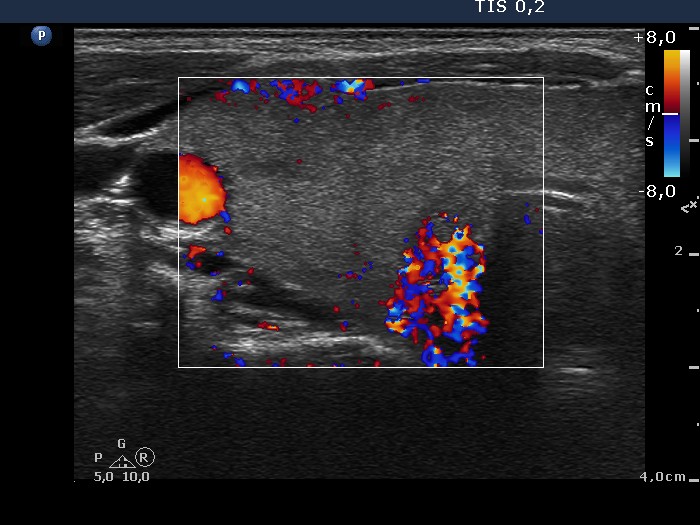

Follow-up investigation 40 months after first visit (ultrasonographic picture 3)

Patient on daily 5 mg methimazole therapy in hypothyroid state

Right lobe, transverse scan, color Doppler mode. The vascularization is minimal.